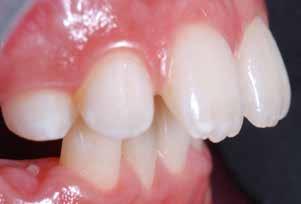

55 54 ESTETICA FUNZIONE POSTURA Valori cefalometrici ad 1 anno di terapia : ANB ANB 3,8 Posizione del Mascellare SNA 91.40 Posizione della Mandibola SNB 87,60 Angolo Articolare SArGo 155,00 Angolo Goniaco ArGoMe 122,00 Angolo incisivo inf^Corpo madibolare IiMand 80,20 Angolo incisivo Sup^Base Cranica Ant. IsCran 111,05 Angolo Interincisivo II 138,00 72, 73 _ Over-bite e over-jet. 74 _ Immagine laterale destra. 75 _ Immagine laterale sinistra. Considerazioni > La terapia precoce di tali malocclusioni è di primaria importanza in quanto impedisce la formazione di malocclu-